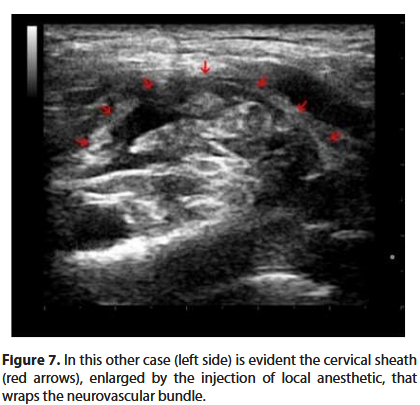

The electrostimulator is set with a current of 0.4 mA. The needle is slowly advanced. When the desired twitch (deltoid, biceps or triceps muscle) appears, the intensity of the current is reduced to below 0.2 mA, until the twitch disappears. In this way we are sure that the tip of the needle is not intraneural. Once the previous stimulation values are restored, 1 ml of anesthetic solution is injected followed by a paraesthesia and the disappearance of the twitch (Raj test) [6]. Only now can we inject the anesthetic solution, witnessing on the screen the expansion of the liquid in the neurovascular bundle (Figures 6 and 7).